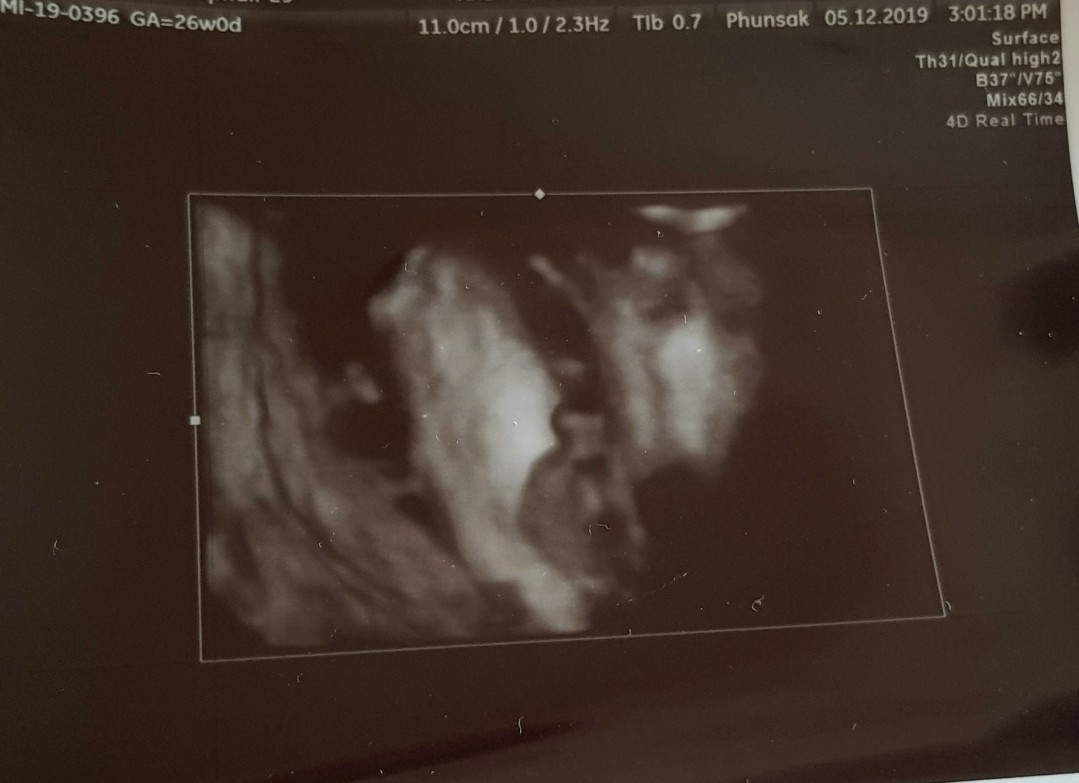

เราชายออกมาแบบนี้เลยจ้าจู๋โผล่

ถ้าเป็นจู๋จะโผล่มาแบบนี้ค่ะ

ญ ค่ะ ถ้าชายแบบนี้